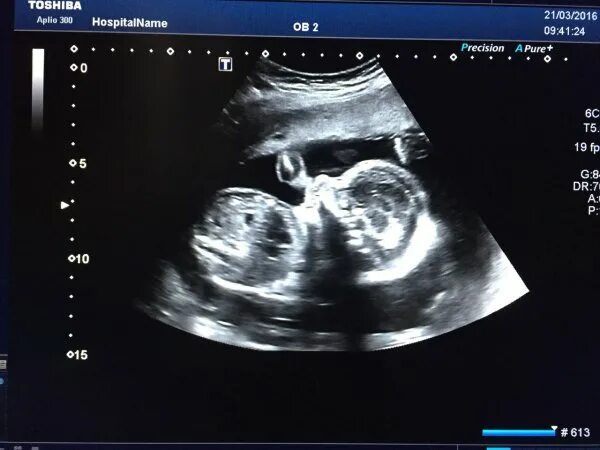

21 неделя 2025г